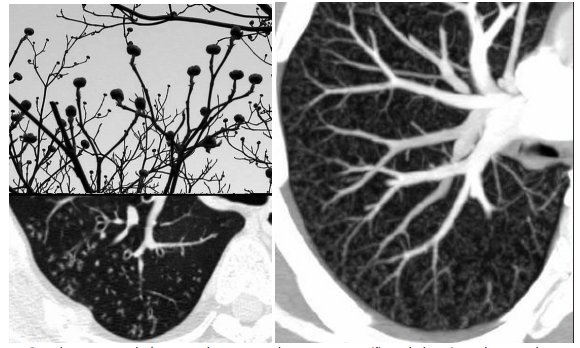

7

Q

Sinais e padrões torácicos

ÁRVORE EM BROTAMENTO

Definição?

A

*Os bronquílos terminais não costumam ser visíveis na TC, no entando se tornam ‘‘indiretamente’’ visíveis quando preenchido (muco, pus, fluidos, etc).

* Formam-se no centro do lóbulo pulmonar secundário

* Poupa parênquima subpleural, incuindo adjacente às fissuras

8

Qual padrão da imagem?

Padrão de árvore em brotamento

* Perceba que poupa as regiões subpleurais